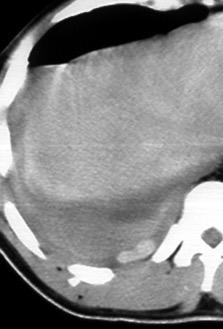

Engrosamiento de la pleura parietal 36/ 59 exudados (61%) 56% de D. paraneumónicos 100% de empiemas Especificidad.. 96%.

Exudado versus trasudado.

Aquino SL, et al. Pleural exudates and transudates: diagnosis with contrast-enhanced CT. Radiology 1994

Signo de la Pleura separada “Split pleural sign”

Capas pleurales de grosor uniforme realzadas por el contraste

No específico de empiema. Indica “exudado”. 68% de pacientes con empiema pleural.

Capas pleurales de grosor uniforme

Realce grasa extrapleural (30%)

> Grasa Extrapleural. (60-80%)

Kraus GJ. Split pleural sign. Radiology 2007